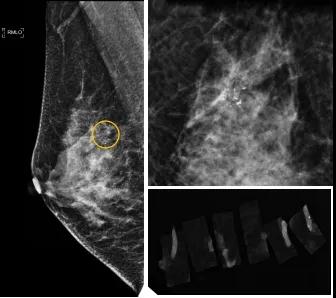

46歲的某女士在西安國(guó)際醫(yī)學(xué)中心醫(yī)院體檢時(shí),行乳腺X線攝影(俗稱(chēng)鉬靶)發(fā)現(xiàn)右乳可疑簇狀鈣化,分布范圍不到1厘米,臨床觸不到,超聲很難發(fā)現(xiàn),但是這種鈣化風(fēng)險(xiǎn)比較高,依據(jù)國(guó)際BI-RADS指南需要明確病理!

西安國(guó)際醫(yī)學(xué)中心醫(yī)院影像診療中心陳寶瑩副主任帶領(lǐng)的團(tuán)隊(duì),采用全數(shù)字化乳腺X線三維立體定位系統(tǒng)可實(shí)施。這個(gè)團(tuán)隊(duì)的成員大部分來(lái)自知名三甲醫(yī)院,有著十余年影像引導(dǎo)下乳腺介入診療的經(jīng)驗(yàn),X線引導(dǎo)穿刺定位和活檢例數(shù)居西北前列。為減少患者創(chuàng)傷,在詳細(xì)判讀了患者資料,并與患者及甲乳外科劉曉敏主任充分溝通的基礎(chǔ)上,團(tuán)隊(duì)確定采用全數(shù)字化乳腺X線三維立體定位系統(tǒng)下實(shí)施粗針活檢。

當(dāng)天,乳腺X線三維立體定位系統(tǒng)清晰顯示出了所有鈣化。為了獲取充足的組織量,保證病理診斷的準(zhǔn)確性,團(tuán)隊(duì)選用14G穿刺針并多點(diǎn)、多角度取材,組織取出后,又立即在高清標(biāo)本攝影系統(tǒng)中進(jìn)行投照,從而確定了取出組織中具有足夠的可疑鈣化。整個(gè)過(guò)程患者無(wú)任何不適,活檢結(jié)束后即回家觀察。

后期病理回報(bào)活檢組織條中均查見(jiàn)導(dǎo)管原位癌。該女士及家屬對(duì)西安國(guó)際醫(yī)學(xué)中心醫(yī)院早期發(fā)現(xiàn)并精準(zhǔn)確診病變的技術(shù)給予了高度的贊揚(yáng)。

乳腺導(dǎo)管原位癌屬于早期的腫瘤性導(dǎo)管內(nèi)病變,有發(fā)展為浸潤(rùn)性癌的傾向,需要早發(fā)現(xiàn)早治療,其預(yù)后明顯優(yōu)于浸潤(rùn)性癌。2020年癌癥雜志的文章指出,近90%的導(dǎo)管原位癌僅表現(xiàn)為不可觸及的可疑鈣化,乳腺X線檢查是發(fā)現(xiàn)微小鈣化最敏感的方式,因此70–90%的導(dǎo)管原位癌是通過(guò)乳腺X線篩查發(fā)現(xiàn)。多年來(lái)國(guó)內(nèi)外指南,如美國(guó)國(guó)家綜合癌癥網(wǎng)絡(luò)(NCCN)指南及中國(guó)抗癌協(xié)會(huì)乳腺癌診治指南均建議40歲以上女性每年通過(guò)雙乳X線檢查(鉬靶)進(jìn)行乳腺癌篩查,高危人群建議提前進(jìn)行篩查(小于40歲)。由于雙乳X線篩查的推廣,歐美等國(guó)家導(dǎo)管原位癌的檢出率極大提高,明顯降低了乳腺癌的死亡率。在我國(guó)規(guī)范進(jìn)行乳腺X線篩查的人群比例比較低,很多人發(fā)現(xiàn)腫瘤時(shí)已經(jīng)為浸潤(rùn)性癌,因此提醒大家高度重視規(guī)范的雙乳X線篩查。通過(guò)乳腺X線篩查發(fā)現(xiàn)的可疑鈣化需要在X線引導(dǎo)下精準(zhǔn)定位,進(jìn)行粗針穿刺或真空輔助旋切活檢,以獲得準(zhǔn)確的病理學(xué)結(jié)果,給予及時(shí)有效的治療。